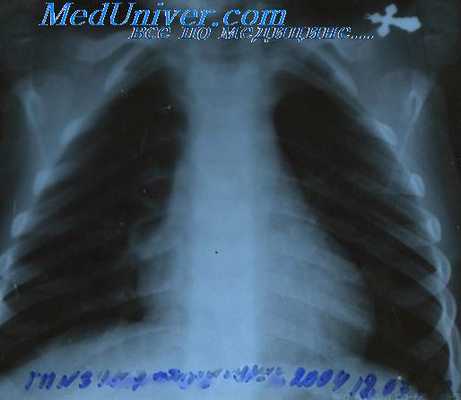

· Рентгенологическое обследование органов грудной клетки (состояние медиастинальных лимфатических узлов, легочной ткани, плевры), включая компьютерную томографию.

- Лимфогранулематоз [болезнь Годжкина (Hodgkin)]. Лимфогранулематоз корней легких может быть одно- и двусторонним. При двусторонней локализации лимфатические узлы при лимфогранулематозе поражены не столь симметрично, как при туберкулезе или при саркоидозе, так что уже сама асимметрия при резко очерченных прикорневых узлах заставляет думать о лимфогранулематозе. Поставить диагноз по клинической картине чрезвычайно трудно, если нет увеличения других лимфатических узлов (аксиллярных, надключичных, вдоль грудино-ключично-сосковой мышцы) или селезенки. Лимфогранулематоз следует предполагать в том случае, если имеются лихорадка интермиттирующего типа (Пель—Эбштейн) и в крови значительная лимфопения (лимфоцитоз почти исключает лимфогранулематоз) и эозинофилия. Однако, если поражены только отдельные узлы, лимфопении и эозинофилии может не быть. Диагноз лимфогранулематоза решает гистологическое исследование. Поэтому необходимо всегда делать пробную биопсию, если узел легко доступен. При соответствующей опытности хирурга биопсия не сопряжена с опасностью, даже если берется прикорневой узел. Прежде чем производить биопсию прикорневого узла, безусловно необходимо раньше прибегнуть к значительно более безобидному вмешательству — пробной биопсии по Daniels. Она проводится на лимфатических узлах, которые всегда имеются в жировой ткани позади места прикрепления m. sternocleidomastoideus на высоте места прикрепления m. scalenus anterior к I ребру. Особенно ценна эта биопсия при лимфогранулематозе (Lageze с сотрудниками). Положительные результаты мы имели также при туберкулезе и бронхогенном раке.